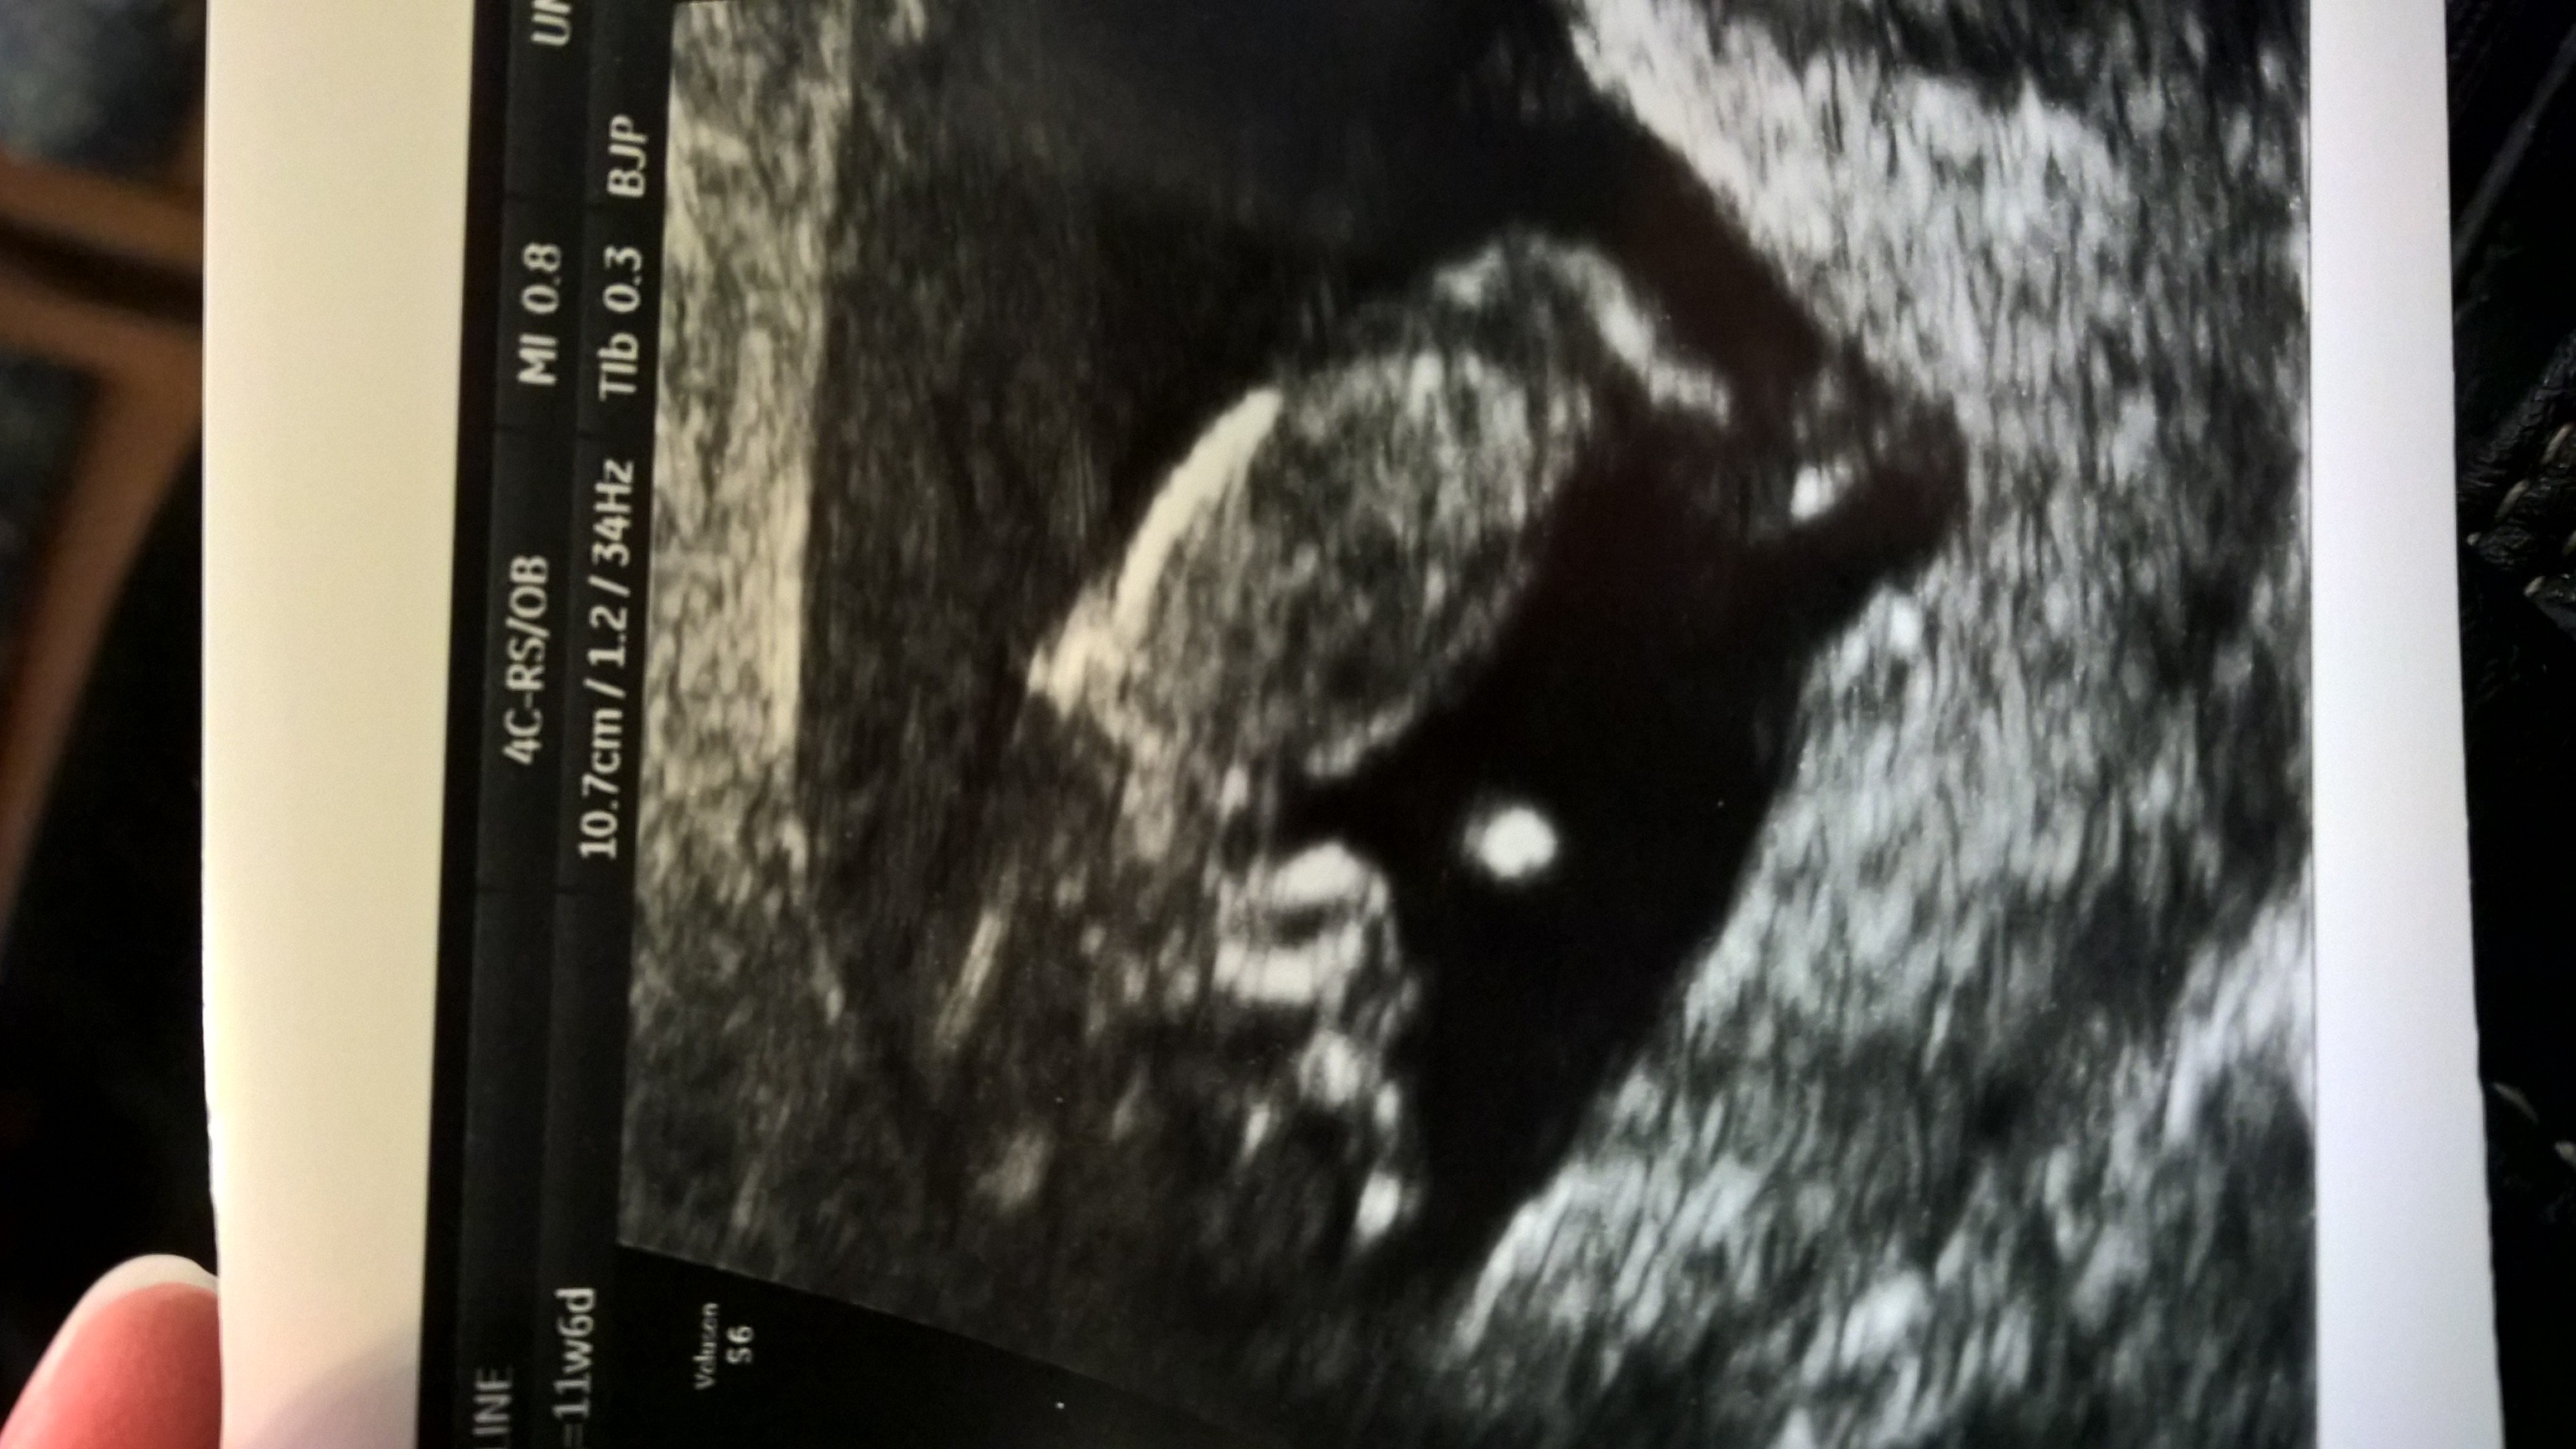

• After a MC in March, I needed this second US to make me feel better about this pregnancy! Loving this little lime - measuring 11w5d